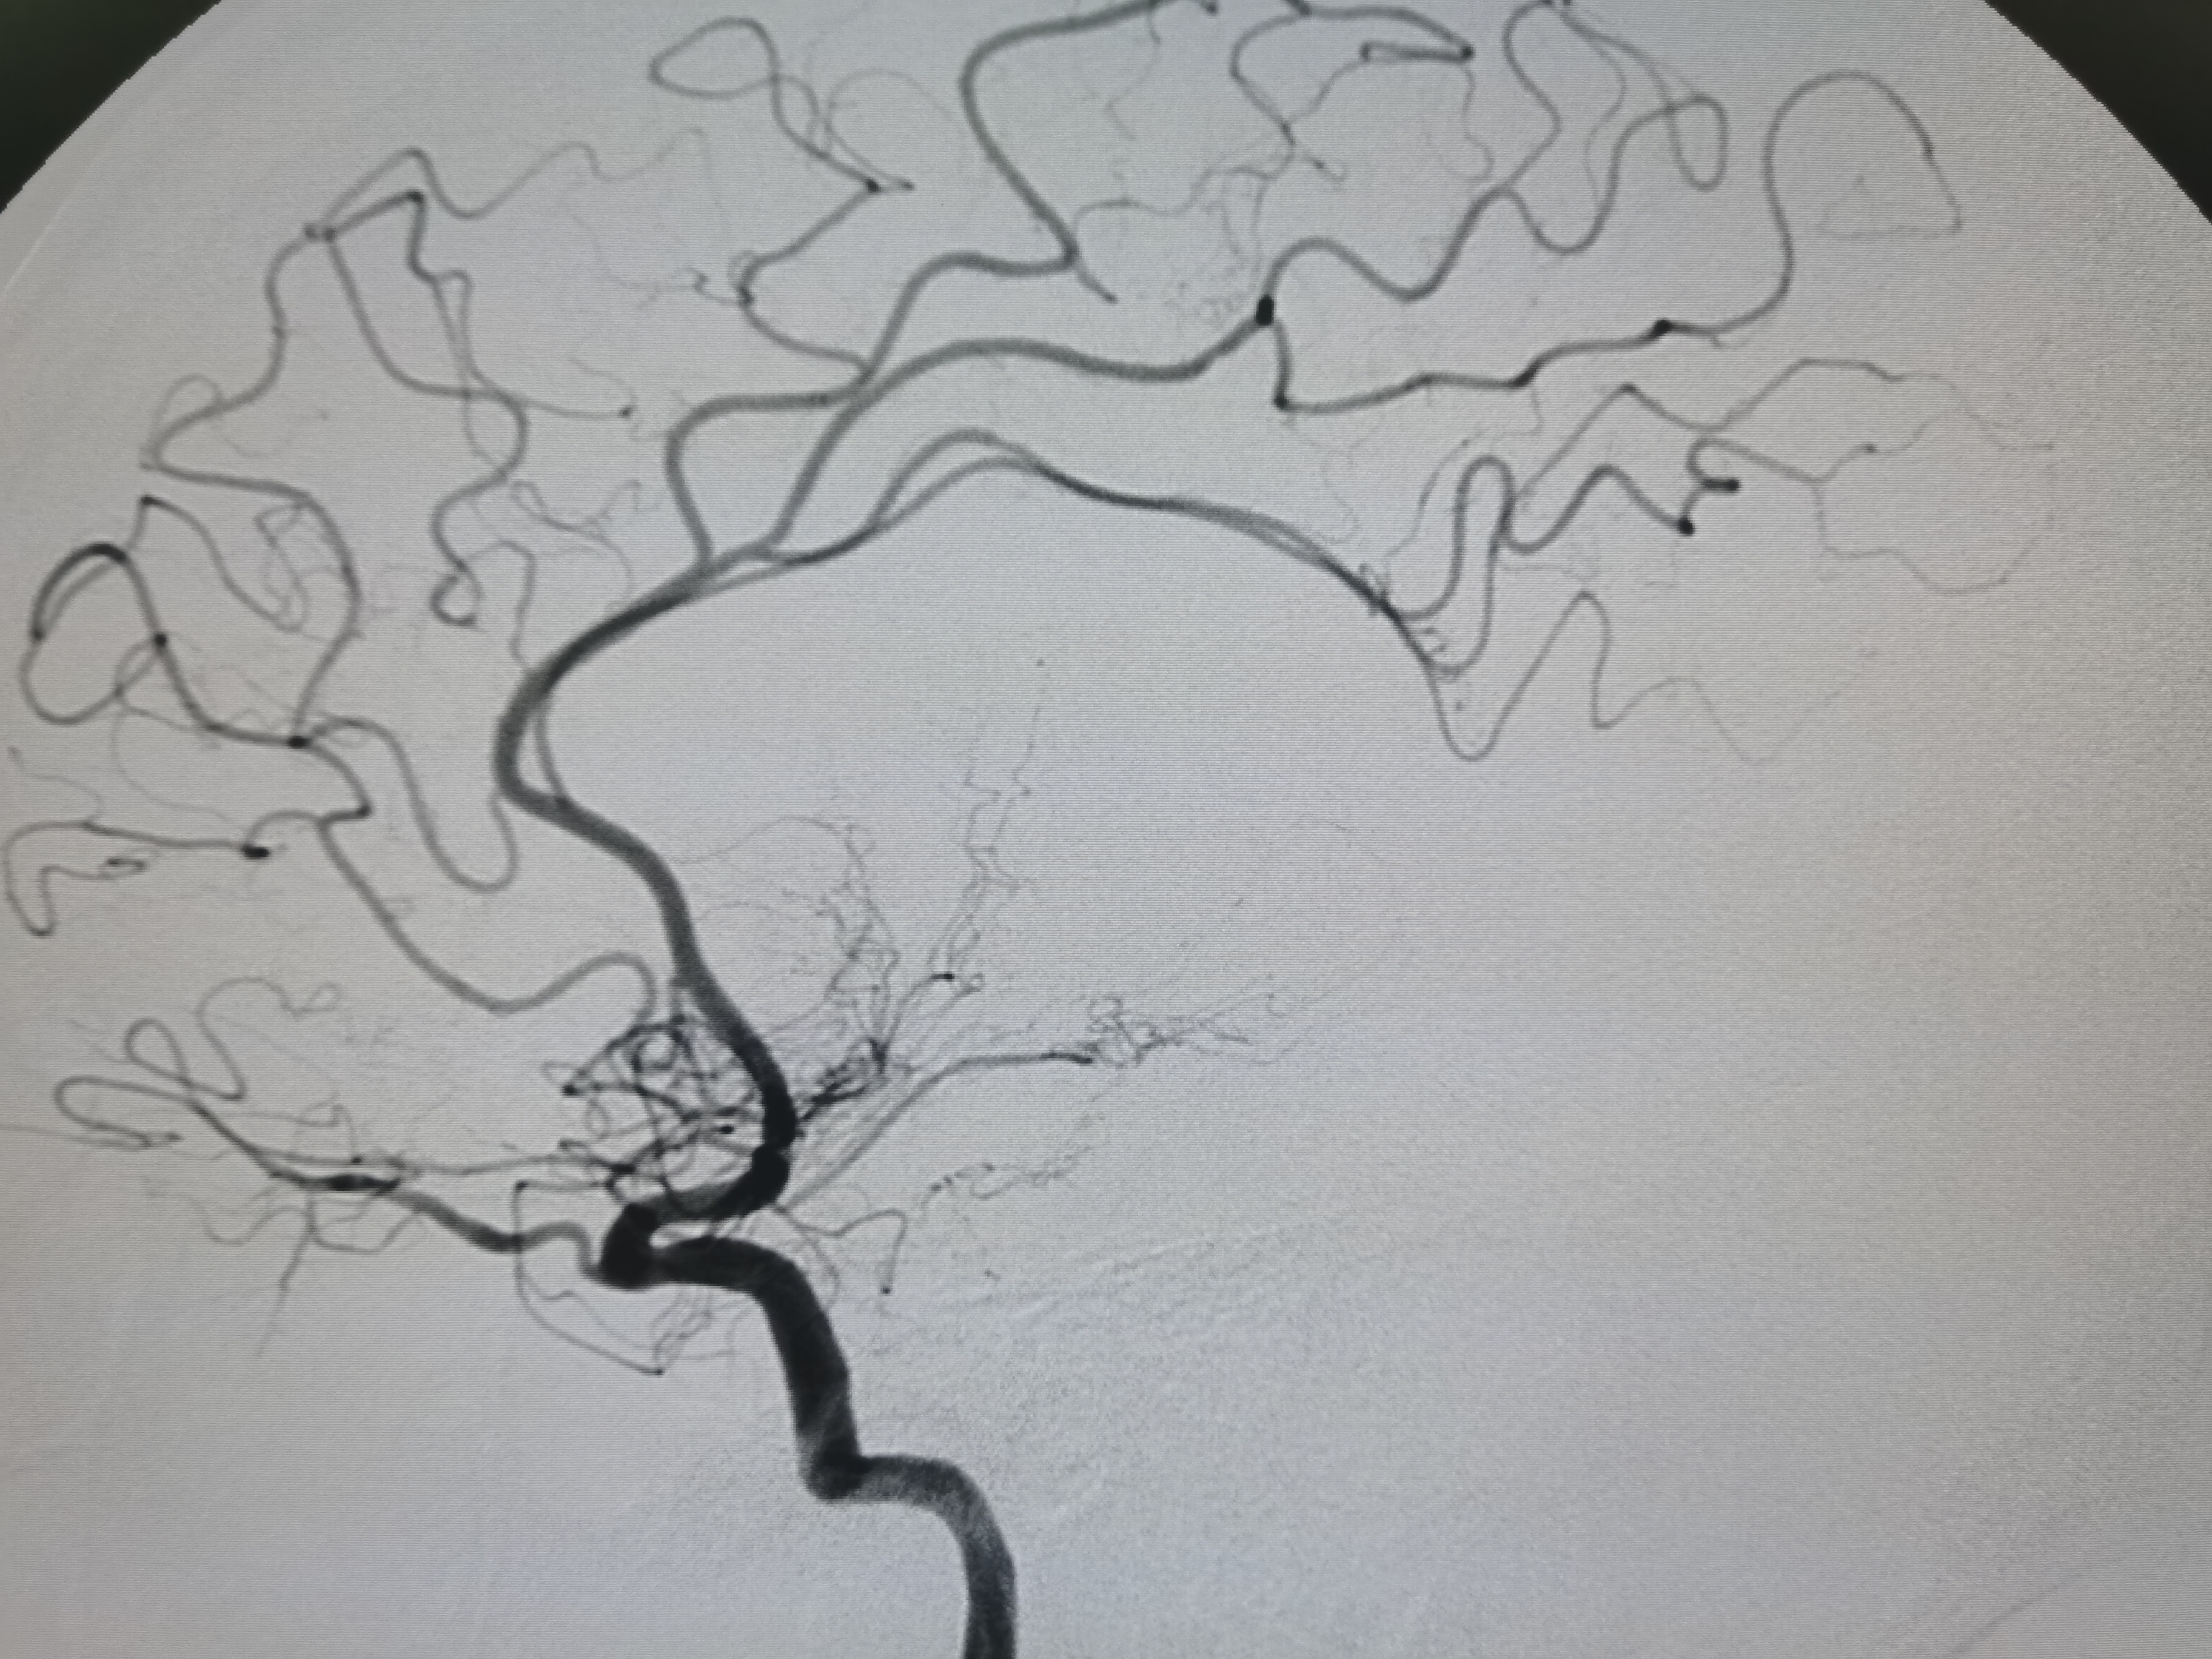

扩张后造影见血管再通,血流通畅。

侧位造影见血流通畅。

观察15分钟后造影血流通畅,未见夹层及明显弹性回缩。

复查造影见颅内狭窄解除,血流通畅,遂未再植入支架,撤出导丝及各级系统,结束手术。患者麻醉苏醒顺利,无新发神经系统症状,给予替罗非班持续泵入,监测生命体征,控制血压避免再灌注损伤。